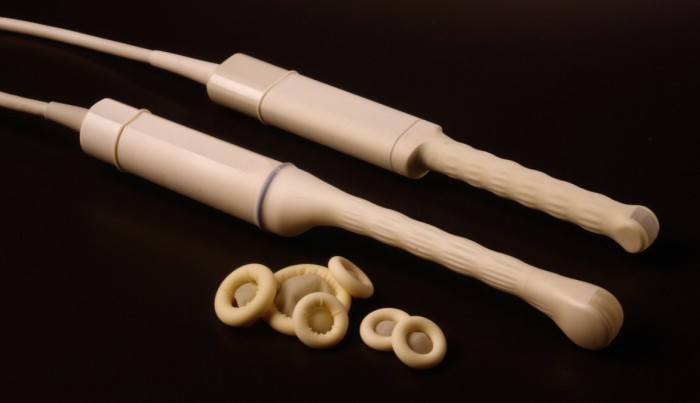

Как же осуществляется данное исследование? В зависимости от того, имеется ли беременность или нет, оно может осуществляться немного по-разному. В частности, речь идет именно о методе исследования. При отсутствии беременности почти всегда используется трансвагинальный метод, так как с его помощью удается достичь максимально близкого расположения датчика к исследуемой области. В результате информативность такого исследования гораздо выше, чем трансабдоминального (в большинстве случаев), при котором картина менее четкая.

В случае отсутствия беременности, как уже упоминалось ранее, назначается трансвагинальное ультразвуковое исследование. Специальная подготовка для этого метода не требуется. В отличие от трансабдоминального исследования, которое необходимо проводить на полном мочевом пузыре, трансвагинальный метод не имеет таких ограничений. Все, что нужно от пациентки – это принести презерватив для использования на датчике в целях гигиены. Также в некоторых медицинских учреждениях могут отсутствовать одноразовые пеленки, поэтому рекомендуется взять с собой полотенце – об этом врач сообщит заранее при назначении процедуры.

Во время исследования пациентка снимает верхнюю одежду и располагается в гинекологическом кресле, на которое заранее укладывается одноразовая простыня, пеленка или полотенце. В влагалище вводится трансвагинальный датчик УЗИ, предварительно помещенный в презерватив и обработанный специальным гелем. Процедура занимает около 10-15 минут, в ходе которой врач визуализирует как шейку матки, так и ее тело. Этот метод позволяет не только оценить биометрические параметры, но и выявить возможные патологии, такие как новообразования или отклонения в состоянии эндометрия и т. д.

Значение такого исследования на разных сроках беременности очень велико. Проводиться оно может трансвагинальным или трансабдоминальным методом. На ранних сроках, обычно, применяется первый способ, как более информативный. На более поздних – второй способ также становится достаточно информативным. Но такое исследование обязательно необходимо выполнять строго на полный мочевой пузырь, так как только таким образом достигается максимальная визуализация исследуемого органа.